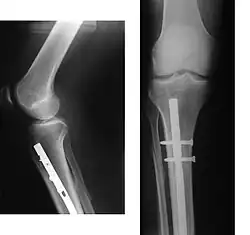

Tratamento cirúrgico

A cirurgia tem por objectivo restabelecer o alinhamento normal do osso, e manter esse alinhamento até a reparação da fratura. Permite também corrigir algumas lesões das partes moles, em especial vasos sanguíneos que possam ter rompido.

O restabelecimento da continuidade óssea por meio cirúrgico (osteossíntese) pode ser feito com recurso a várias técnicas, habitualmente com a utilização de placas e parafusos, varetas endomedulares ou Fios de Kirschner.